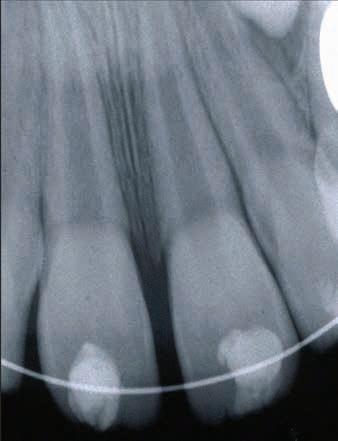

Due to the severity of intrusion, the treating dentist decided to perform surgical repositioning and stabilize with a physiologic splint. Local anesthesia was achieved with the use of 20% topical benzocaine gel and infiltration with 25 mg of 2% lidocaine with 1:100,000 epinephrine. Surgical repositioning of the maxillary left permanent central incisor was achieved with the use of gentle force with straight maxillary forceps (#99C). Figure 2 shows the position of the tooth after surgical repositioning.

A 0.016” Nitinol wire with bonded composite resin was used to secure the repositioned tooth. The physiologic splint engaged all the 4 maxillary permanent incisors. The radiograph in Figure 3 shows the repositioned tooth with splint in place. The patient was very anxious about feeling pain and about how much it would hurt. However, the pediatric dentist was able to use basic behavior guidance techniques such as tell-show-do, verbal reassurance and positive reinforcement to complete the treatment.

Figure 2. Position of the intruded tooth after surgical repositioning.

Figure 3. Radiograph of repositioned tooth with physiologic splint in place.